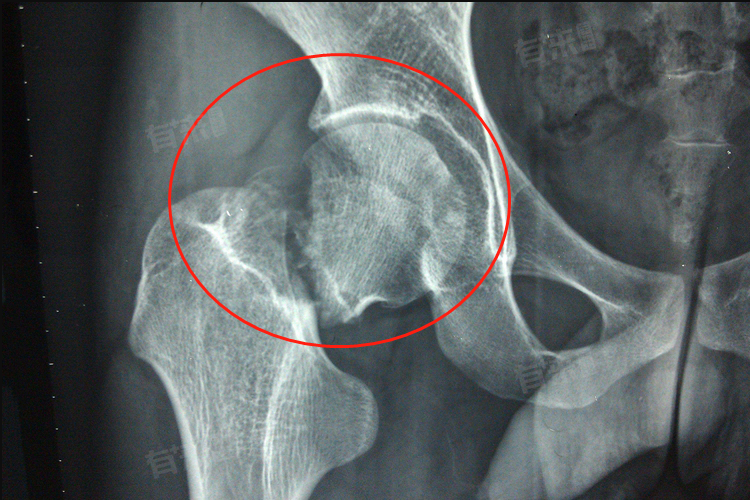

右股骨颈骨折的治疗方法,主要分为保守治疗和手术治疗两大类,患者应当及时到医院就诊,经医生评估后选择综合治疗措施,以促进骨折部位愈合。

- 切开复位内固定:适用于青壮年及骨折移位明显的患者,通过手术切口暴露骨折部位,移除碎骨片后使用螺钉、钢板等内固定器材恢复骨骼解剖位置。

- 关节置换:包括全髋置换和半髋置换,尤其适用于老年患者。老年患者由于骨质疏松和骨折愈合能力差,易发生股骨头坏死,关节置换成为首选,该方法可以重建关节功能,使患者尽早下床活动,减少长期卧床带来的并发症。